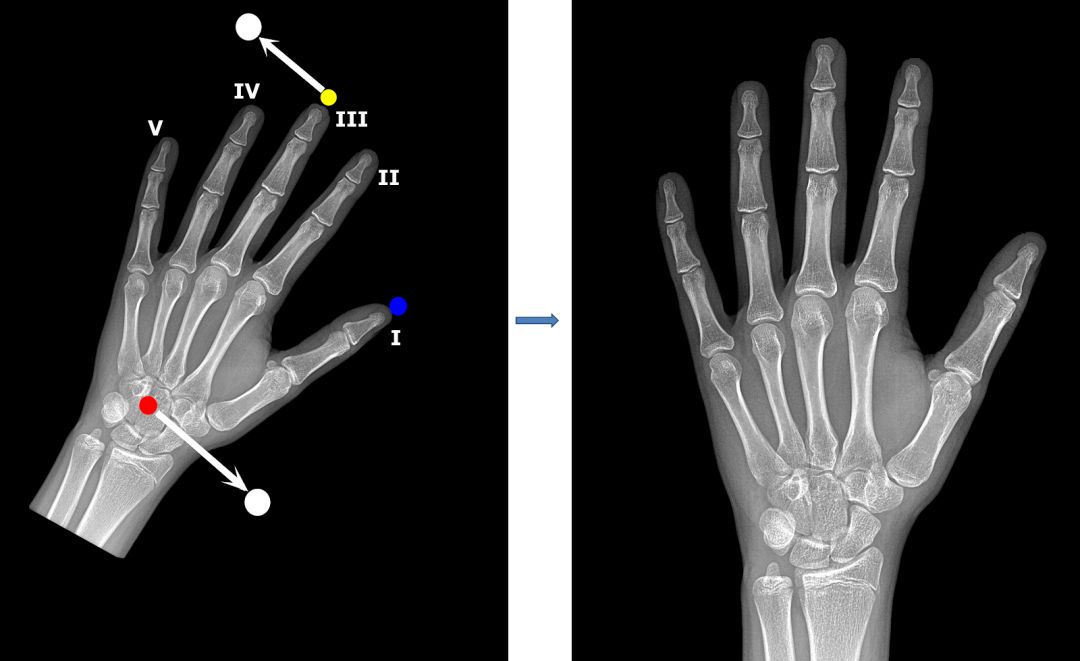

预处理 II:基于特征点进行图像配准

我们的图像配准策略很简单:检测手骨中几个特征点的坐标,然后计算仿射变换参数(缩放、旋转、平移和反射),使图像与标准位置一致。

为了创建特征点模型的训练集,我们用 VGG 图像注释器(VIA)手动标注了 800 张放射影像。我们选择了三个特征点:第三根手指远端指骨的顶端,拇指远端指骨的顶端以及头状骨的中心。我们将特征点的像素坐标作为回归模型的训练目标。

为了提升泛化性能,我们对输入应用了包括旋转、平移和缩放在内的标准增强。模型输出 6 个坐标,即 3 个特征点中每个特征点有 2 个坐标。

找到特征点后,我们就可以计算所有放射影像的仿射变换(缩放、旋转、平移)。我们的目标是在保持图像纵横比的情况下,将其调整到统一的位置:

1. 中指顶端水平对齐,在图像上边缘以下约 100 个像素处。

2. 头状骨水平对齐,在图像下边缘以上约 480 个像素处。

通常用左手的放射影像评估骨龄,但有时候数据集中的图像会呈镜像。为了检测这些图像并对其进行适当调整,我们使用拇指作为特征点。

来看一个图像配准模型起作用的例子。如你所见,手骨成功地旋转到我们希望的标准位置了: